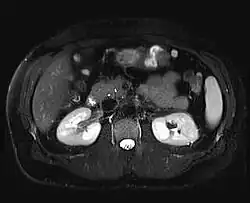

Magnetická rezonance (též MR, MRI, z anglického „magnetic resonance imaging“) je zobrazovací technika používaná především ve zdravotnictví k zobrazení vnitřních orgánů lidského těla. Pomocí MRI je možné získat řezy určité oblasti těla, ty dále zpracovávat a spojovat až třeba k výslednému 3D obrazu požadovaného orgánu. Magnetická rezonance využívá silné statické magnetické pole (řádově jednotky T) a elektromagnetické vlnění (s frekvencemi v řádu desítek až stovek MHz). Na rozdíl od CT vyšetření, které je s MR někdy alternativní, nenese žádná rizika způsobená ionizačním zářením (nulová radiační zátěž). Nevýhodou vyšetření MR je určitá hlučnost zařízení. Podstatou odlišení jednotlivých tkání a patologií je jejich rozdílné chování při stejném vnějším působení. Vyšetření se provádí bez kontrastní látky nebo s ní (např. gadolinium vpichem do žíly).

Použitím gradientních magnetických polí v přesně specifikovaných okamžicích vyšetření se v různých místech sledované oblasti těla dočasně a řízeně změní velikost magnetického pole a tím i rezonanční frekvence jader. Změřené frekvence indukovaného napětí se výpočtem převedou na polohu v obraze a amplituda napětí se zobrazí na škále šedé. Různé úrovně šedé potom svědčí o různých vlastnostech měřených tkání. K interpretaci obrazů používá zejména sledování rozhraní, na kterých se mění intenzita signálu.